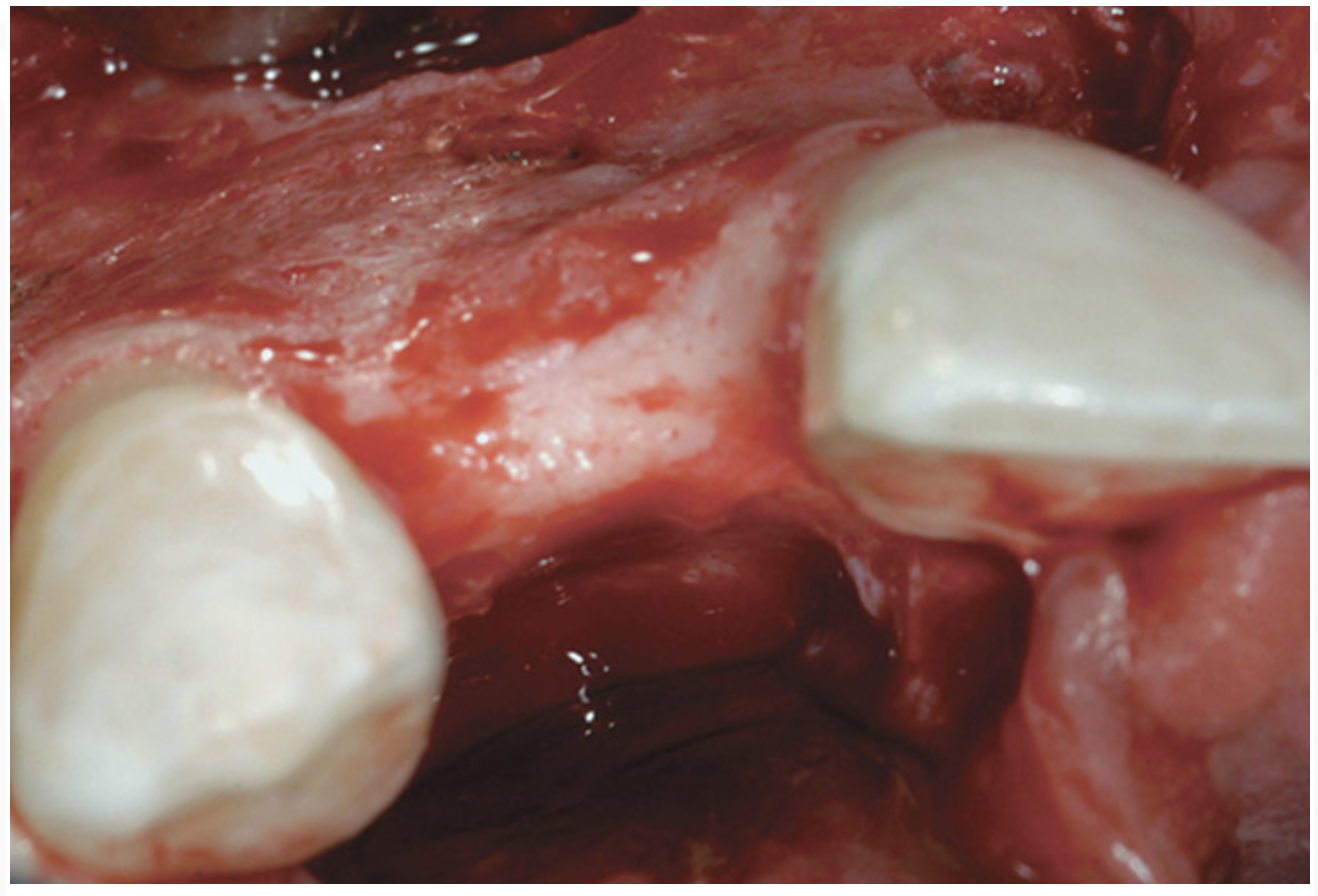

Case 1

A 16-year-old female patient with a congenitally missing maxillary right lateral incisor was referred for an implant-supported crown. Clinical and CBCT evaluation revealed both a facial and palatal bony width deficiency (Figure 2 and Figure 3). The treatment plan included the use of titanium mesh and rhBMP-2/ACS (INFUSE® Bone Graft) along with mineralized allograft (MinerOss®, BioHorizons, www.BioHorizons.com) for bony augmentation (Figure 4 and Figure 5). After 7 months, the graft was found to be well incorporated and allowed for placement of a 3.8-mm x 10.5-mm diameter root form implant that was restored 3 months later (Figure 6, Figure 7, Figure 8, Figure 9 and Figure 10).

Figure 2  Congenitally missing maxillary right lateral incisor.

Figure 2

Figure 6  Facial and palatal alveolar ridge width deficiency.

Figure 6